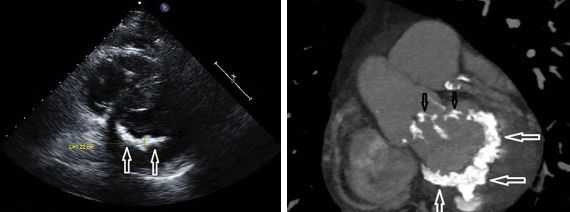

- эхокардиографии с допплер-анализом - ключевых исследований в диагностике пролапса митрального клапана, которые позволяют определить степень пролабирования клапанных створок и объем крови, поступающей в левый желудочек при регургитации;

Другой важный инструментальный метод диагностики — эхокардиография (Эхо-КГ) . Эхо-КГ — это безболезненное ультразвуковое исследование, которое позволяет исследовать работу сердца в реальном времени. Эхокардиография покажет уменьшение эластичности клапана, его повреждение, размер отверстия митрального клапана и расстояние между его створками. Также при исследовании можно увидеть разрыв папиллярной мышцы и провисание клапанных створок в полость левого предсердия [4] [8] [9] .

- Эхокардиография (УЗИ сердца). Здесь врач может обнаружить такие признаки болезни, как провисание створок митрального клапана (задней или сразу обеих) в полость левого предсердия в середине систолы, в позднюю систолу или во всю систолу. Эхокардиография - это одно из самых важных обследований в диагностике ПМК у пациента.